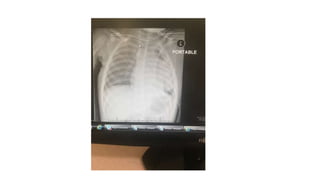

Chest US ,CT both suggest a pleural effusion (proteinacious) with

minimal septae

• Was taken for VAST , drained 1000ml of pus

Chest US ,CTboth suggest a pleural effusion (proteinacious) with minimal septae

• Was takenfor VAST , drained 1000ml of pus